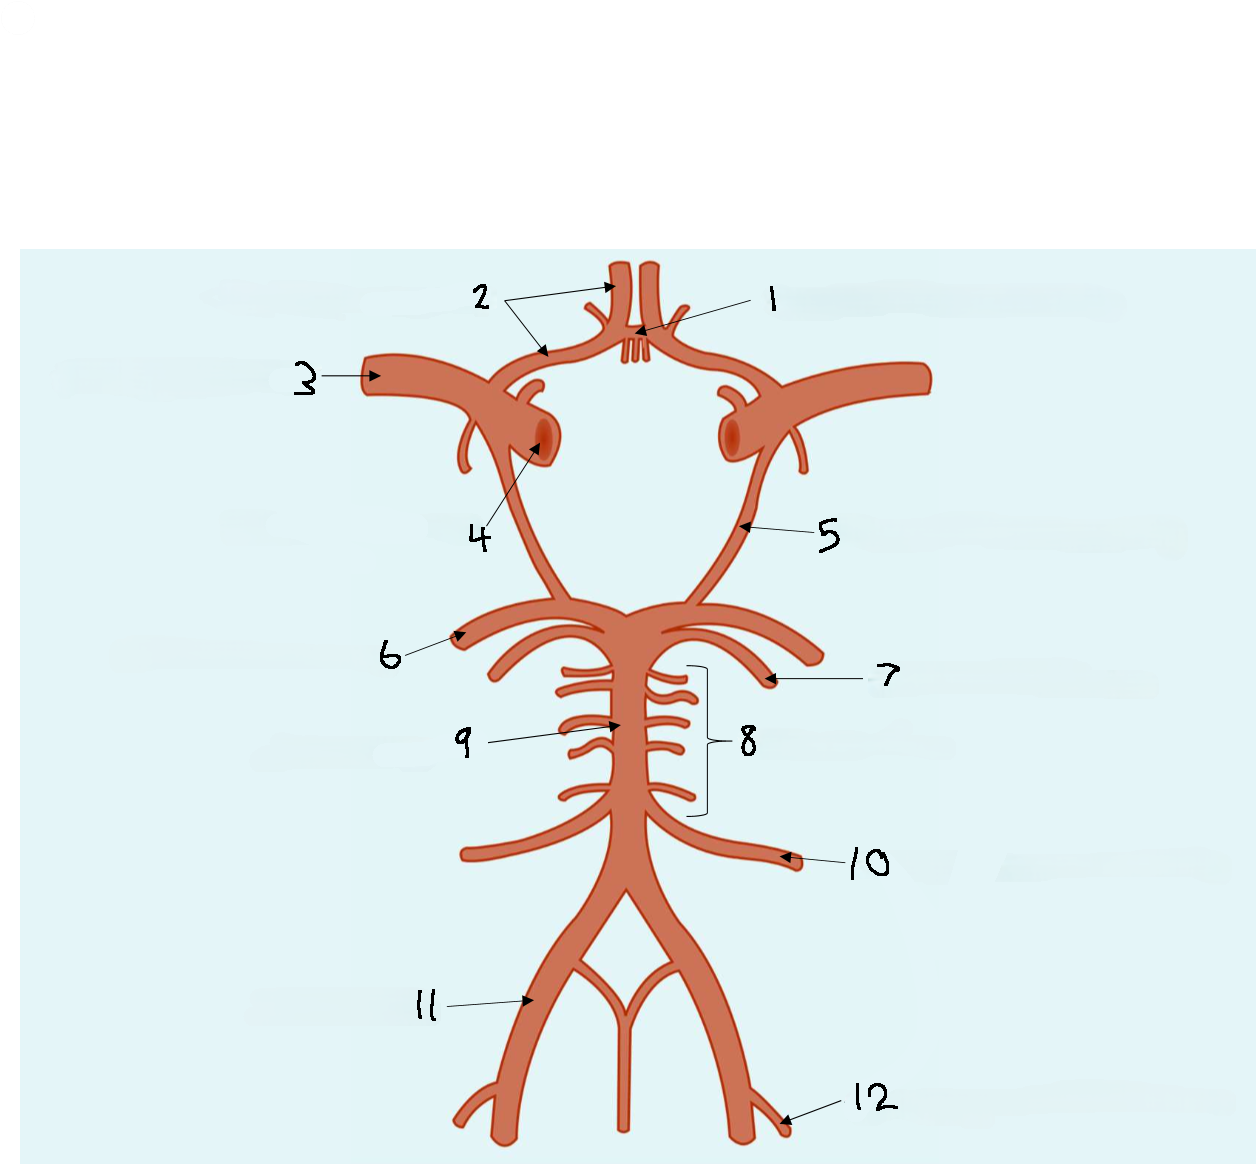

What is 1?

anterior communicating artery

What is 2?

anterior cerebral artery

What is 3?

middle cerebral artery

What is 4?

internal carotid artery

What is 5?

posterior communicating artery

What is 6?

posterior cerebral artery

What is 7?

superior cerebellar artery

What is 8?

pontine arteries

What is 9?

basilar artery

What is 10?

anterior inferior cerebellar artery

What is 11?

vertebral artery

What is 12?

posterior inferior cerebellar artery